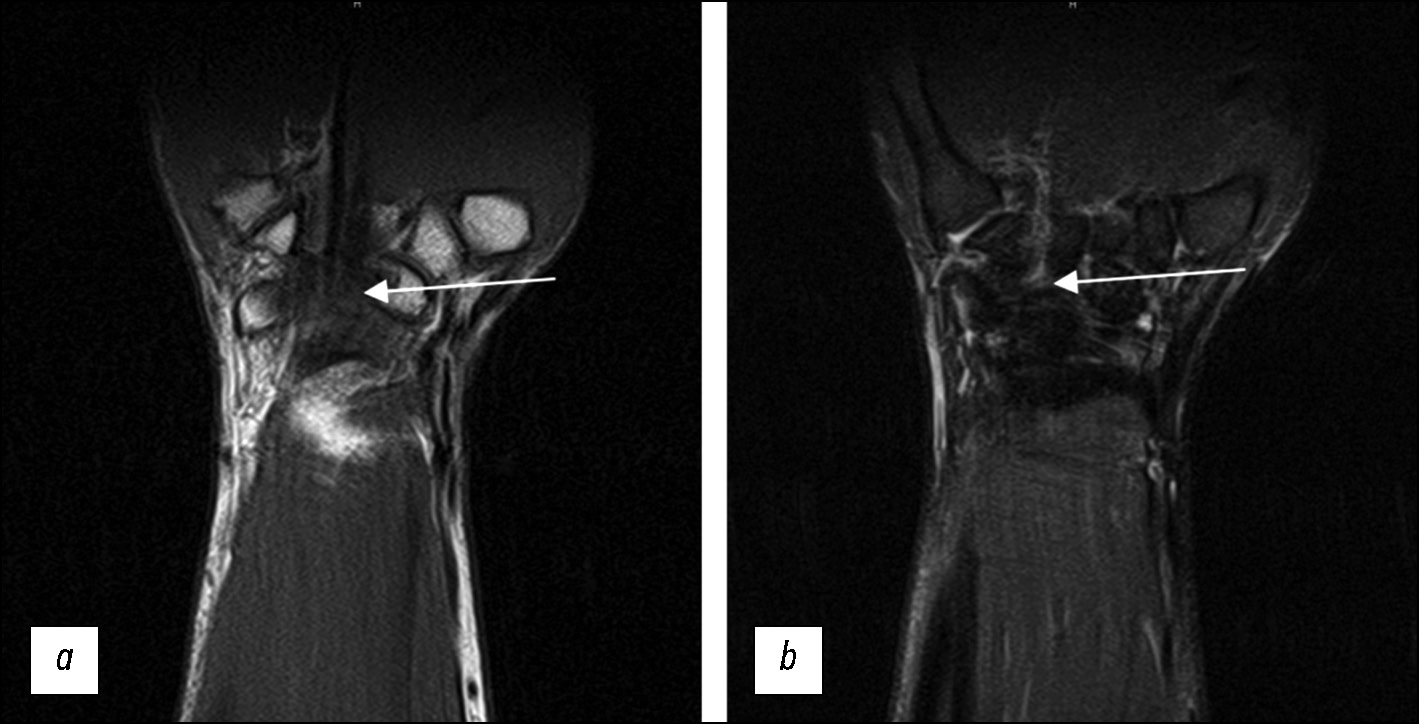

Fig. 8. Reduced imaging quality because of movement artifacts without using a splint (arrows); (a) T1-weighted images in the coronal plane; (b) STIR protocol in the coronal plane.

Fig. 9. Reduced imaging quality in a patient with triangular fibrocartilage complex disorder because of motion artifacts (arrows) and atypical positioning (without a splint); (a) T2-weighted images in the coronal plane; (b) PD-weighted images with fat suppression in the sagittal plane.